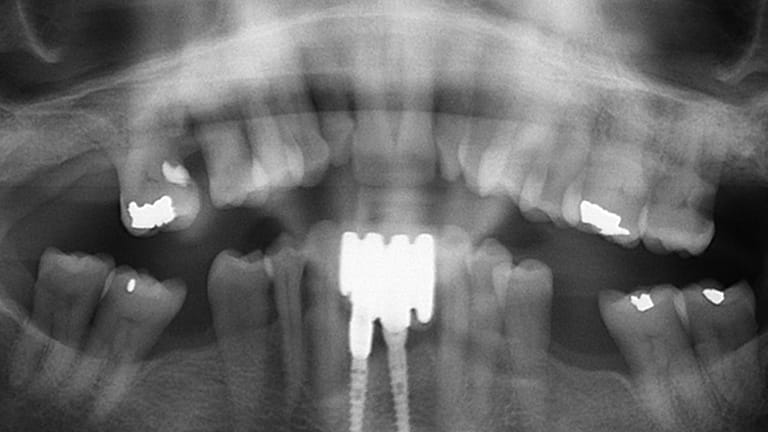

Dental implants are a titanium "root" which can be placed into the jawbone. Once integrated with your bone, the implant can be used to support a crown, a bridge, or secure a complete denture. Dental implants may be used to eliminate partial plates and dentures. The success rates for dental implants are extremely high which is due in part to the fact that root-form implants are made of a biocompatible material, titanium.

Implant (With no crown)

Implant with crown